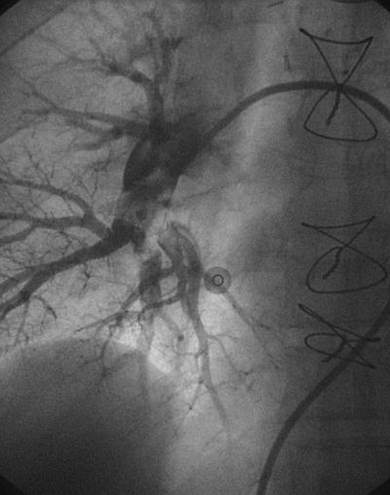

Angiografía de la arteria pulmonar derecha realizada con un catéter en espiral de 6 F en ángulo, que demuestra la presencia de un trombo de gran tamaño dentro de la arteria pulmonar derecha y en las bifurcaciones lobulares intermedia, inferior y superior.

Se efectuó una trombectomía reolítica con el catéter PE de AngioJet® mediante un catéter guía multifunción de 8 F y una guía de angioplastia hidrófila de 0,035’’, en las bifurcaciones lobulares intermedia e inferior.

Angiografía pulmonar derecha realizada tras una trombectomía reolítica en la que se muestra la mejora de los índices de perfusión y obstrucción.